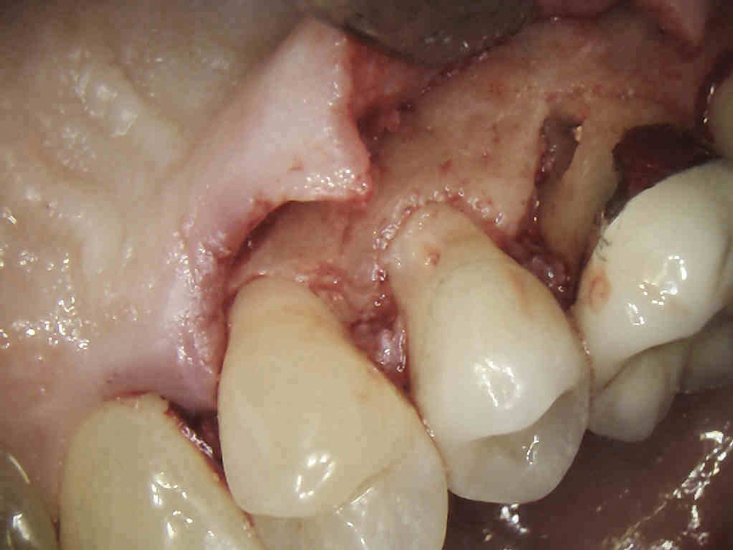

(4.) The granulation tissue was removed in its entirety, and the defects were treated with a 90% TCA solution.

Figure 4

(5.) The defects were filled with a bioactive, biocompatible calcium silicate-based restorative cement.

Figure 5